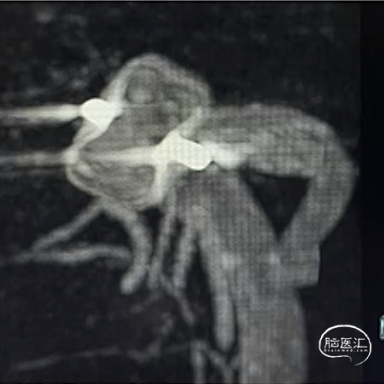

经测量可得动脉瘤宽度平均值为7.0mm,动脉瘤高度为5.18mm,选用WEB™ SL 8*4。

WEB™经由VIA™微导管送入动脉瘤瘤腔并完全释放。术后即刻造影显示WEB™尺寸合适,贴壁良好,分支等血流通畅。解脱后再次造影,可见动脉瘤瘤腔内有明显造影剂滞留。

术后3个月随访,WEB™完全栓塞,动脉瘤完全闭塞。